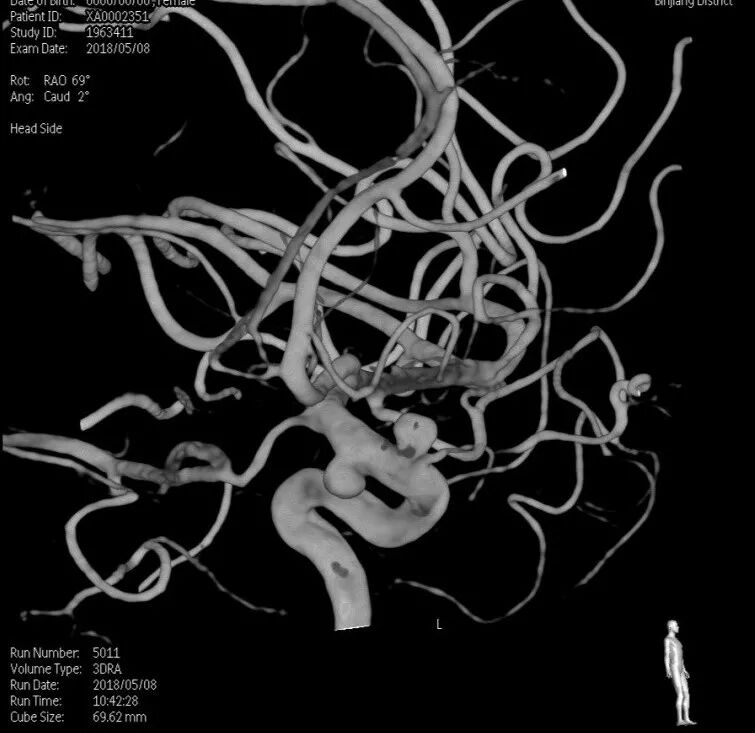

入院后完善DSA检查提示颅内多发动脉瘤:右侧颈内动脉眼段大动脉瘤(约18*19mm,瘤颈6.6mm),左侧眼动脉段及床突段动脉瘤。和家属沟通病情,告知介入和开颅手术风险利弊后,患者家属选择开颅动脉瘤夹闭手术治疗。进一步行DSA+CT融合,模拟手术入路视角。

术前MRA和CTA

右侧眼动脉瘤

左侧眼动脉段及床突段动脉瘤

术前融合后模拟开颅骨窗

术前融合后模拟显微镜视角

术前科室讨论:根据患者术前DSA+CT融合图像,左侧动脉瘤因右侧巨大动脉瘤及骨性结构的遮挡,无法手术夹闭。拟先行右侧动脉瘤夹闭。但右侧动脉瘤体型巨大,位于眼段床突旁,临近颅底,术中需要磨除床突,但可能诱发瘤体破裂,若无法有效阻断血流,极可能出现致死性出血。可考虑术前暴露颈总动脉分叉部,术中临时夹阻断颈内动脉,但增加了手术创伤。建议利用复合手术室优势,术中介入球囊临时阻断颈内动脉后行动脉瘤夹闭。

结合本病例,我们术前利用复合手术室飞利浦DSA血管机,造影后即刻行CT扫描。由于是在同一机器环境下完成的两种模态扫描,减少了伪影干扰,解剖结构电脑自动吻合,故影像融合精度极高。并且因为是双模态融合,可以用不同颜色标记血管和骨窗,增加了对比度,提高了分辨率,较CTA有明显优势。利用术前融合模拟手术入路,放大后观察发现动脉瘤体巨大,紧贴颅底和床突,缺乏至少2mm的近端阻断空间,术中需要磨除前床突。但术中发现动脉瘤表面张力极高,紧贴床突硬脑膜,高速磨钻操作存在巨大风险。而术中球囊阻断颈内动脉后,动脉瘤张力明显下降,依靠吸引器轻轻牵拉即可暴露出瘤颈,不必要磨除床突,降低了手术复杂度。